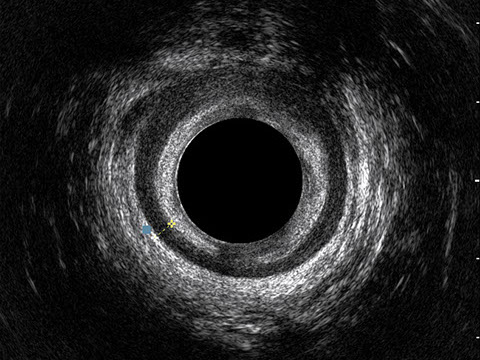

L’ecografia transanale è un esame diagnostico per immagini che consiste nell’introduzione di un trasduttore ad ultrasuoni. Le immagini qualitativamente migliori del canale anale sono ottenute usando un trasduttore rotante, montato in un manipolo rigido, che fornisce un’immagine a 360°. Con le apparecchiature più moderne è anche possibile ottenere immagini tridimensionali.

L’ecografia transanale permette di distinguere la sottomucosa che riveste il canale anale, lo sfintere anale interno, e lo sfintere anale esterno.

Le principali indicazioni all’esecuzione di tale esame sono lo studio dell’integrità delle strutture muscolari nei casi di incontinenza fecale, lo studio topografico dei processi settici perianali (ascessi e fistole) e lo studio dei processi proliferativi epiteliali (carcinoma anale).